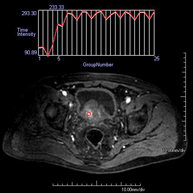

- RM Pelvis femenina

Prueba diagnóstica no invasiva que consiste en la obtención de imágenes de alta definición anatómica de la pelvis mediante el empleo de un campo electromagnético y ondas de radio (con un emisor y un receptor). No utiliza radiación ionizante. Se realiza para estudiar patologías del útero, del ovario, de las trompas y la vagina, ya sean de origen tumoral, inflamatorio o vasculares. Además permite valorar les estructuras adyacentes localizadas en la pelvis, identificando sus alteraciones. A veces requiere el uso de contraste intravenoso (Gadolinio) para caracterizar las lesiones.

- RM Pelvis masculina

Prueba diagnóstica no invasiva que consiste en la obtención de imágenes de alta definición anatómica de la pelvis masculina mediante el empleo de un campo electromagnético y ondas de radio (con un emisor y un receptor). No utiliza radiación ionizante. No requiere de preparación previa. En algunas ocasiones requiere el empleo de contraste paramagnético (Gadolinio) para caracterizar las lesiones. Esta prueba permite valorar órganos como la vejiga urinaria, la unión entre los uréteres y la vejiga, la próstata, las vesículas seminales, la uretra, los huesos de la pelvis, etc.